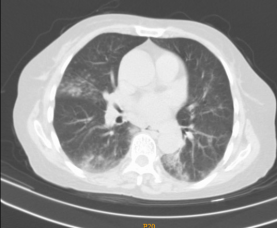

一、胸部CT:双肺散在小斑片密度增高影,以双下肺、右肺中叶为甚,边缘模糊。颈根部、纵隔内多发淋巴结,部分肿大,大者位于气管隆突下。